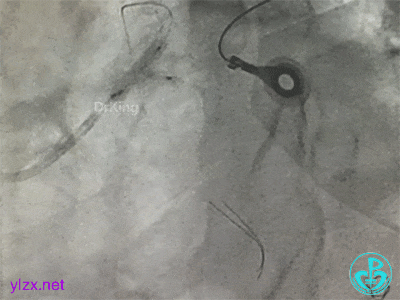

左主干分叉病变采取Crush双支架术式,回旋支开口植入支架,前降支开口球囊挤压后左主干到前降支植入支架(Crush双支架术式)。

导丝准备穿支架网眼Rewire回旋支时患者血压继续下降。去甲肾上腺素微量泵剂量逐渐增大至25ml/h,立即置入IABP,血压回升后再继续操作。